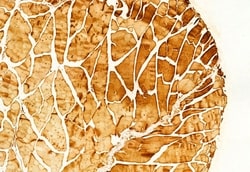

Antibody detects endogenous levels of total RAB9B.

| Applications | Immunohistochemistry (Paraffin), Western Blot, Immunocytochemistry |